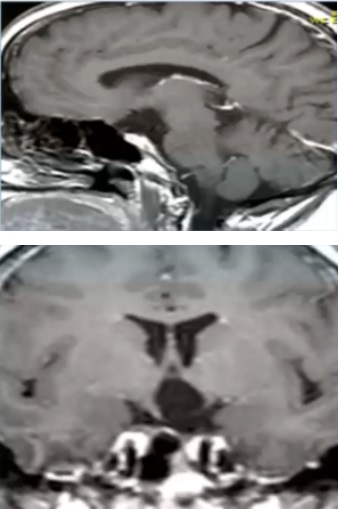

术前MRI

术后MRI,显示解剖性全切除